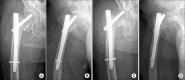

Methods: Eighty-two patients with intertrochanteric fractures that were treated with intramedullary hip nails between December, 2004 and January, 2011 were subjected to this study. The patients who could be followed for a minimum of one year postoperatively were enrolled. The immediate postoperative conditions were determined by radiograms: reduction status (3 parameters/4 points: contact accuracy of posteromedial cortex, severity of angulation, and distraction), fixation status (3 parameters/3 points: tip-apex distance, location of tip of the lag screw, entry point of the intramedullary nail), and fracture type (1 parameter/1 point: stable or unstable type by the Kyle's classification). Postoperative reduction loss and fixation failure were checked by radiograms taken at a minimum 3 months postoperative.

Results: Reduction loss and fixation failure were observed in 14 consecutive patients (17%). The fixation failure rate was 100% (2 patients) in score 1, 60% (3 out of the 5 patients) in score 2, 39% (3 out of the 8 patients) in score 3, and 50% (4 out of the 8 patients) in score 4 groups. There were fixation failures only in 1 out of 13 patients with score 5, and in 1 out of 18 patients with score 6. There was no fixation failure in 17 patients with score 7 and 11 patients with score 8.

Conclusions: Maintenance of the fracture reduction by the stable fixation in the patient scores over 5 could be predicted by the postoperative radiograms.